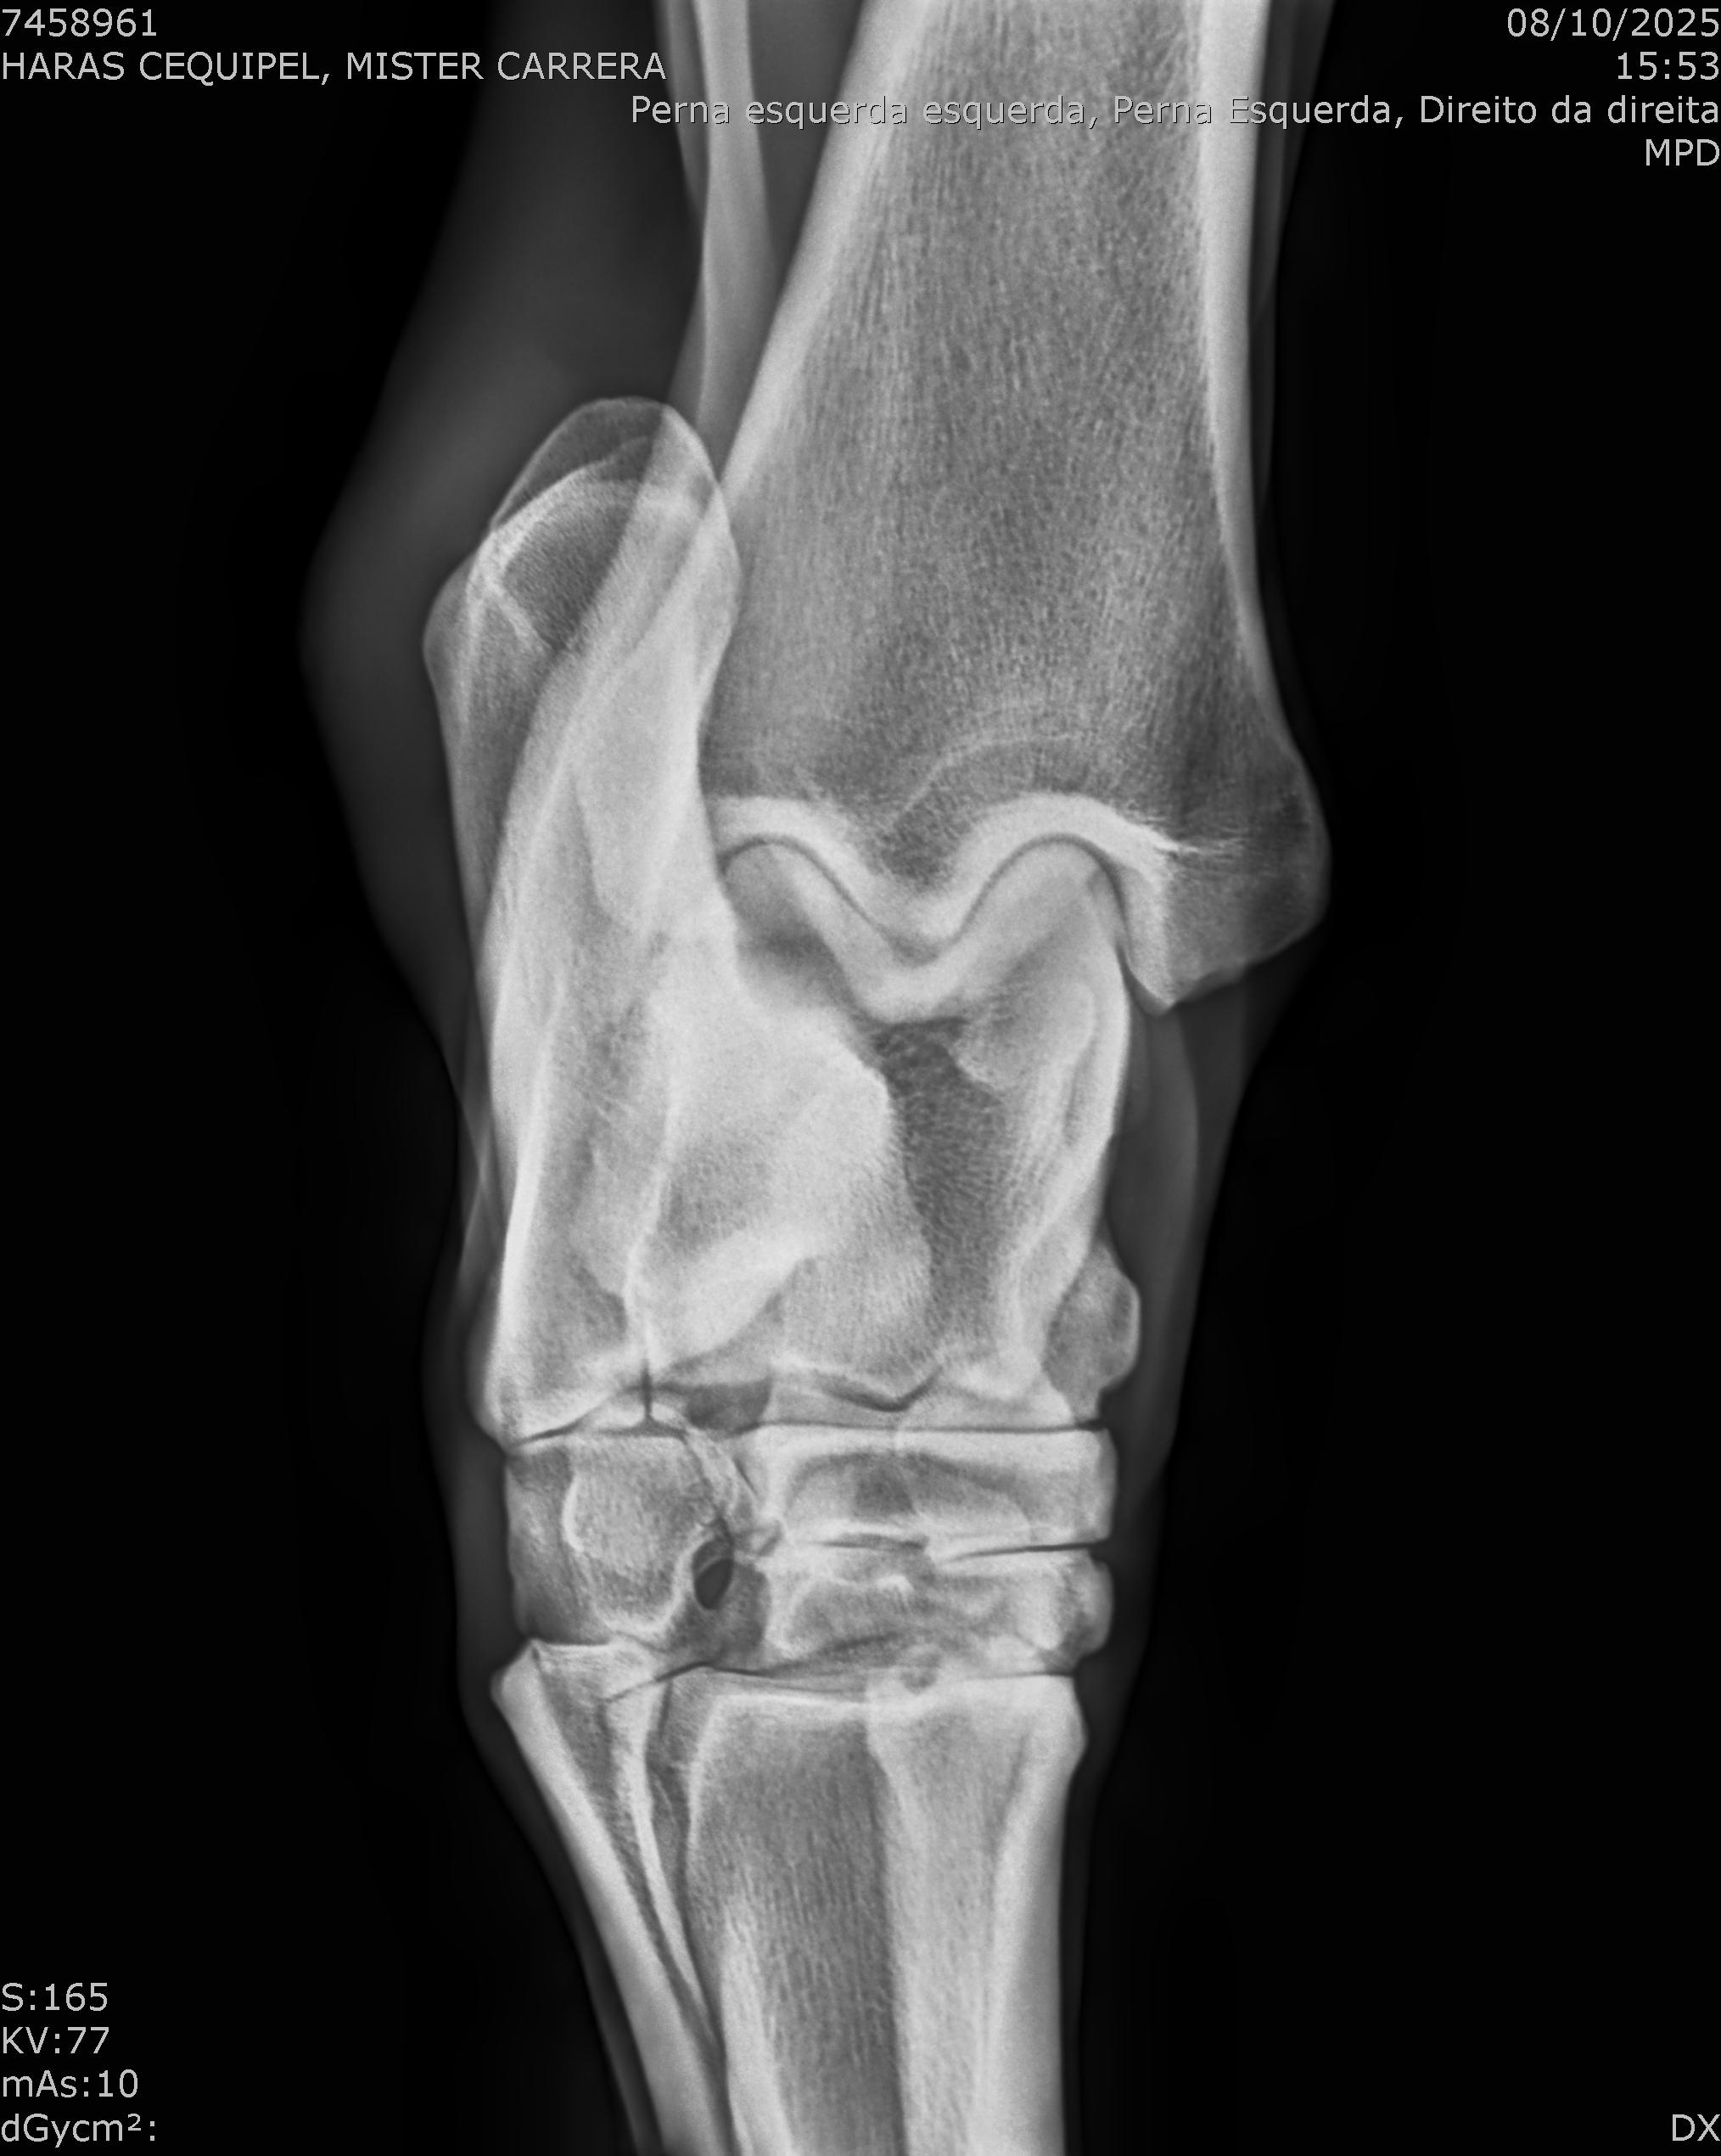

:: RAIOS-X DO LOTE